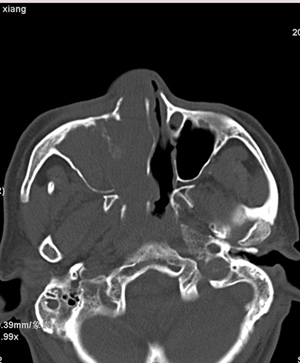

以下是引用影象小辈在2008-5-4 13:34:00的发言:[br]鼻腔及右侧上颌窦 筛窦内软组织密度影, 相邻鼻中隔、鼻甲及窦壁骨质破坏吸收,病灶延伸至鼻咽腔及右侧眼眶 多考虑为1.乳头状瘤 2.息肉 建议增强及活检

以下是引用peijunlong在2008-5-4 13:35:00的发言:[br]考虑右侧鼻腔内翻性乳头状瘤[br]好发:中老年人。[br]ct:1:一侧鼻腔内肿块经扩大的自然孔道长入鼻窦,是其顺自然孔道蔓延的特点[br] 2:鼻腔,鼻窦扩大,窦壁压迫性骨质破坏。[br] 3:广泛生长的肿瘤可侵犯邻近结构,如眼眶、翼腭窝和颅内。

以下是引用不学无术在2008-5-4 20:43:00的发言:[br]病人已在齐鲁医院穿刺活检病理结果:中分化鳞癌。